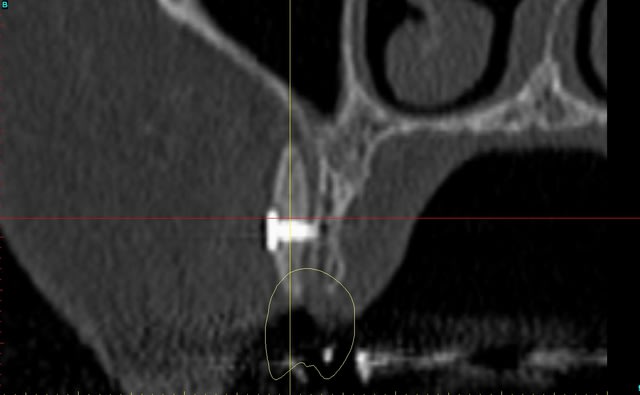

Dar axial lebnbu - Eugenol

Dar axiali qui1is - Eugenol

Dar11 cyo3el - Eugenol

Dar13 alznrp - Eugenol

Dar13i aujibg - Eugenol

Dar14 actm24 - Eugenol

Dar15 zvi82y - Eugenol

Dar23i g6nxds - Eugenol

Dar24 vzfroa - Eugenol

Dar25 lcptyk - Eugenol

Dar 3d xkb3uv - Eugenol

Dar  3di ngfcc4 - Eugenol

Dar  3dl fwmdk6 - Eugenol

Céramik

image 8, il semble y avoir une zone entre le greffon et l'os ?

C'est intégré ?